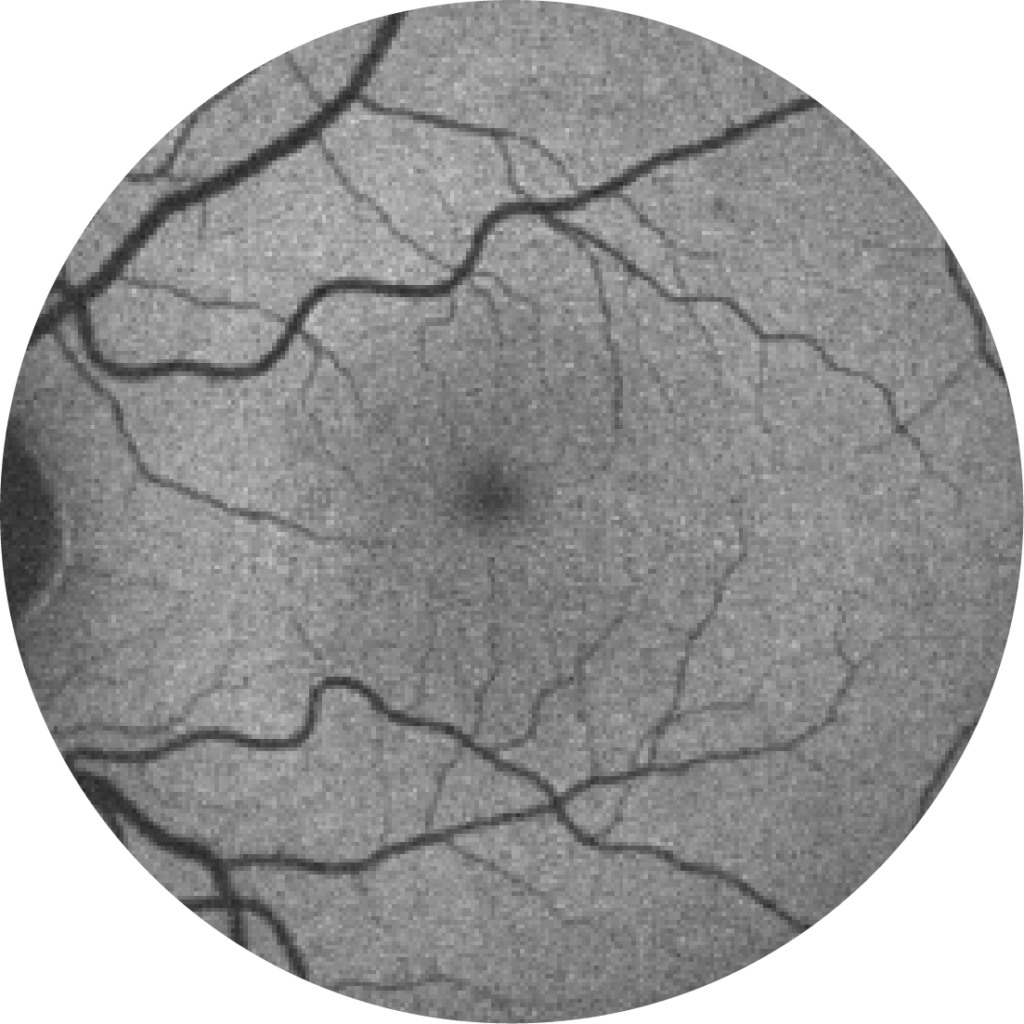

Fundus photograph of a healthy eye

Fundus photograph of an eye with geographic atrophy

When diagnosing and monitoring age-related macular degeneration an ophthalmologist, retinal specialist or optometrist will look for the following features in the retina:19

• Decorated with drusen

• A sharply demarcated area in the macular region with an atrophic retina, lacking pigmentation

• Visible underlying choroidal blood vessels